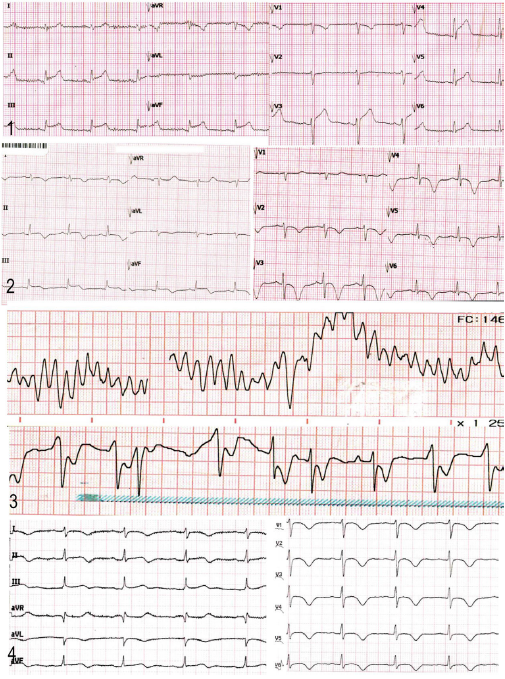

Figura 2 Evolución temporal del trazado electrocardiográfico del caso presentado. En el primer trazado (A) (día 1) se evidencia la presentación inicial con patrón de elevación del segmento ST en la cara inferior. En el segundo trazado (B) (día 3) se observa alteración de la repolarización en las derivadas precordiales con ondas T invertidas y profundas, además de la prolongación del intervalo QT. El tercer trazado (C) (día 13) representa el segundo ingreso a urgencias, cuando la paciente presentó paro cardiorrespiratorio secundario a una arritmia maligna: taquicardia ventricular polimórfica, que se revierte con desfibrilación. El cuarto trazado (D) (día 15) muestra la persistencia de la alteración de la repolarización miocárdica y del intervalo QT prolongado más allá de la etapa subaguda de la enfermedad.